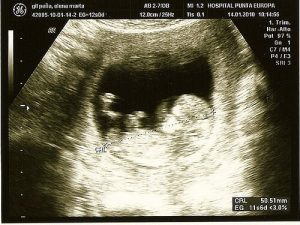

Ultrason:

Karnınızdaki bebeğinizin ilk görüntüsünü görmenizi sağlayan bu test aynı zamanda da birçok sorunu belirlemede kullanılan son derece yaygın bir prosedürdür.

Bu prosedür çiftlerin, bebeklerinin cinsiyetini öğrenmesine de olanak sağlar. Bebeğin kalbinde oluşabilecek bir sorun gibi çeşitli anomalileri ve kromozomlarda meydana gelebilecek değişimleri belirleme konusunda çok yararlıdırlar.

Fetüsteki olası bazı bozukluk ya da sorunların daha detaylı gözlemlenebilmesi adına ikinci seviye ultrason testleri yapılması tavsiye edilir. İkinci seviye ultrason testleri, tarama testlerinin belirlediği olası sorunları daha detaylı araştırmak adına uygulanırlar.

Ultrason testi, ses ötesi dalgalar vasıtası ile görüntü yaratan noninvazif (müdahalesiz) bir tekniktir.